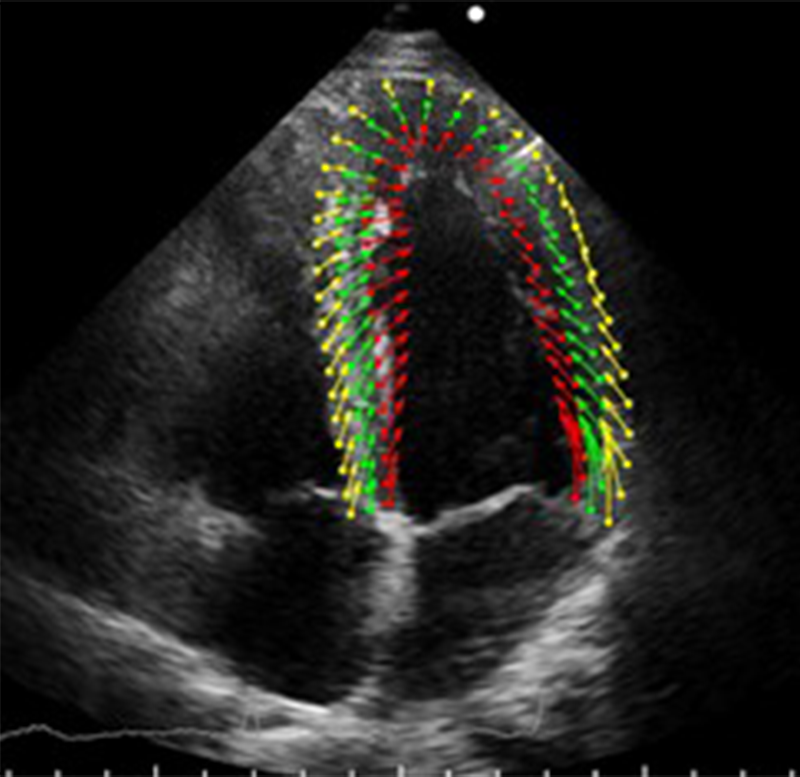

- トラッキングの安定化:次に、図2のように、トラッキング点の座標の動きベクトルから心筋の輪郭点上の動きベクトルを算出する(赤緑黄矢印)。各色の配列は、内膜、中層、外膜に相当する。ここで、図1の多数のトラッキング点の動きベクトルの中には、本来と動きが異なるトラッキングエラーも含まれている。そこで、エラーベクトルの除去と平均化を行うことによって、エラーの影響を低く抑え、近傍の動きベクトルが揃うような安定したトラッキングを実現している。

図2 図1の動きベクトルから算出した内膜、中層、外膜の動きベクトル

(図1と同一時相、ベクトルの長さは実際の10倍で表示)